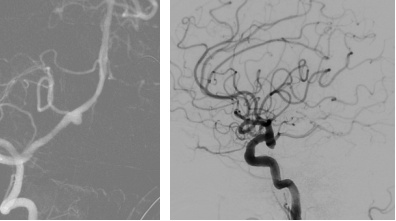

术后,医疗团队又为他进行了

脑部钻孔引流和腰大池置管引流

简单理解

就是在颅骨上开一个小孔

并放置一根细细的引流管

目的是把大脑周围刺激性的

积血引流出体外

为大脑恢复创造条件

经过31天惊心动魄的抢救与康复

这位曾濒临死亡的患者

最终自己走出了医院